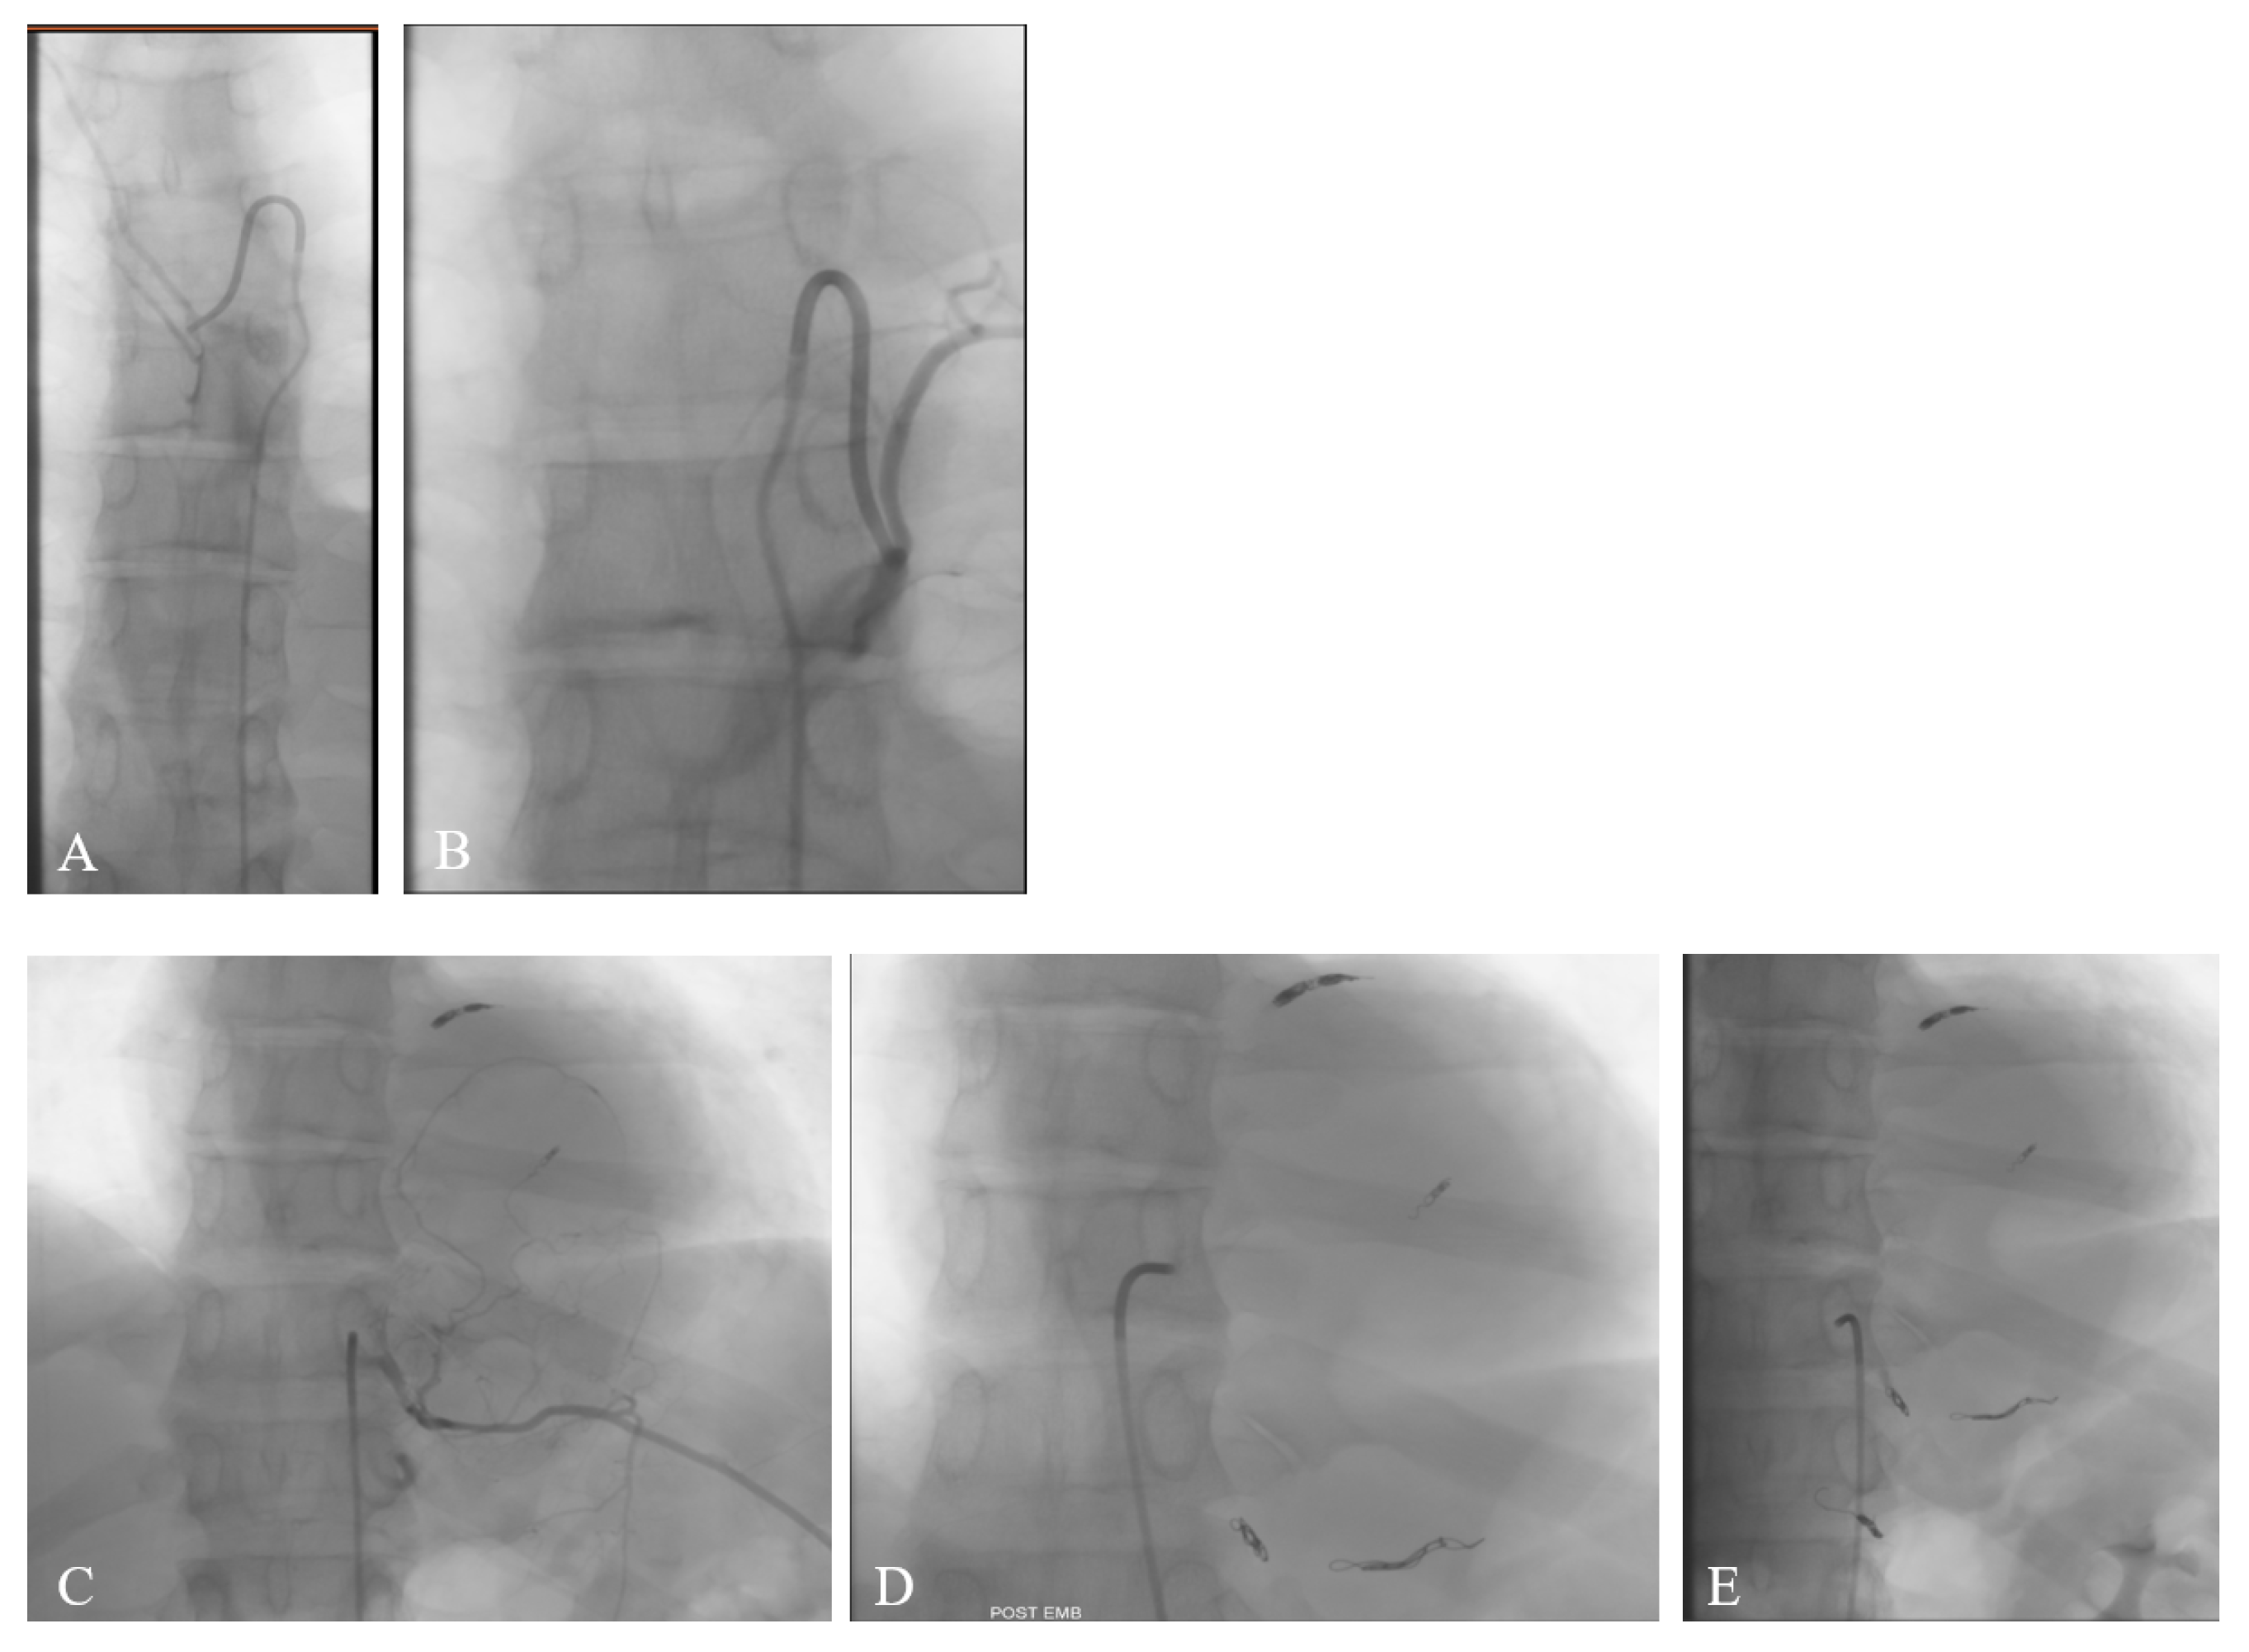

We requested the angiographic study to assess the origin of the anterior spinal artery (Figure 2A,B), as this information crucial for surgical planning and minimizing the risk of spinal cord ischemic damage. The angiography demonstrated that the vascular afferences to the anterior spinal artery originated from the left T7 and T9, and the right T12 and L3 arteries. Based on the vascular pattern and tumor hypervascularization demonstrated during the angiographic study, the interventional radiologist decided to proceed with embolization (Figure 2C–E) to reduce intraoperative bleeding and facilitate tumor resection. Embolization of the tumor’s feeding branches from the left T10, T11, and T12—avoiding the left T9 supply to the anterior spinal artery—was performed using multiple coils, successfully excluding the blood supply to the mass.

Figure 2. Angiography demonstrated that the arterial supply to the anterior spinal artery originated from the left T7 and T9 (A,B), and the right T12 and L3. Embolization of the tumor’s feeding branches from the left T10, T11, and T12 was performed using multiple coils (CE).